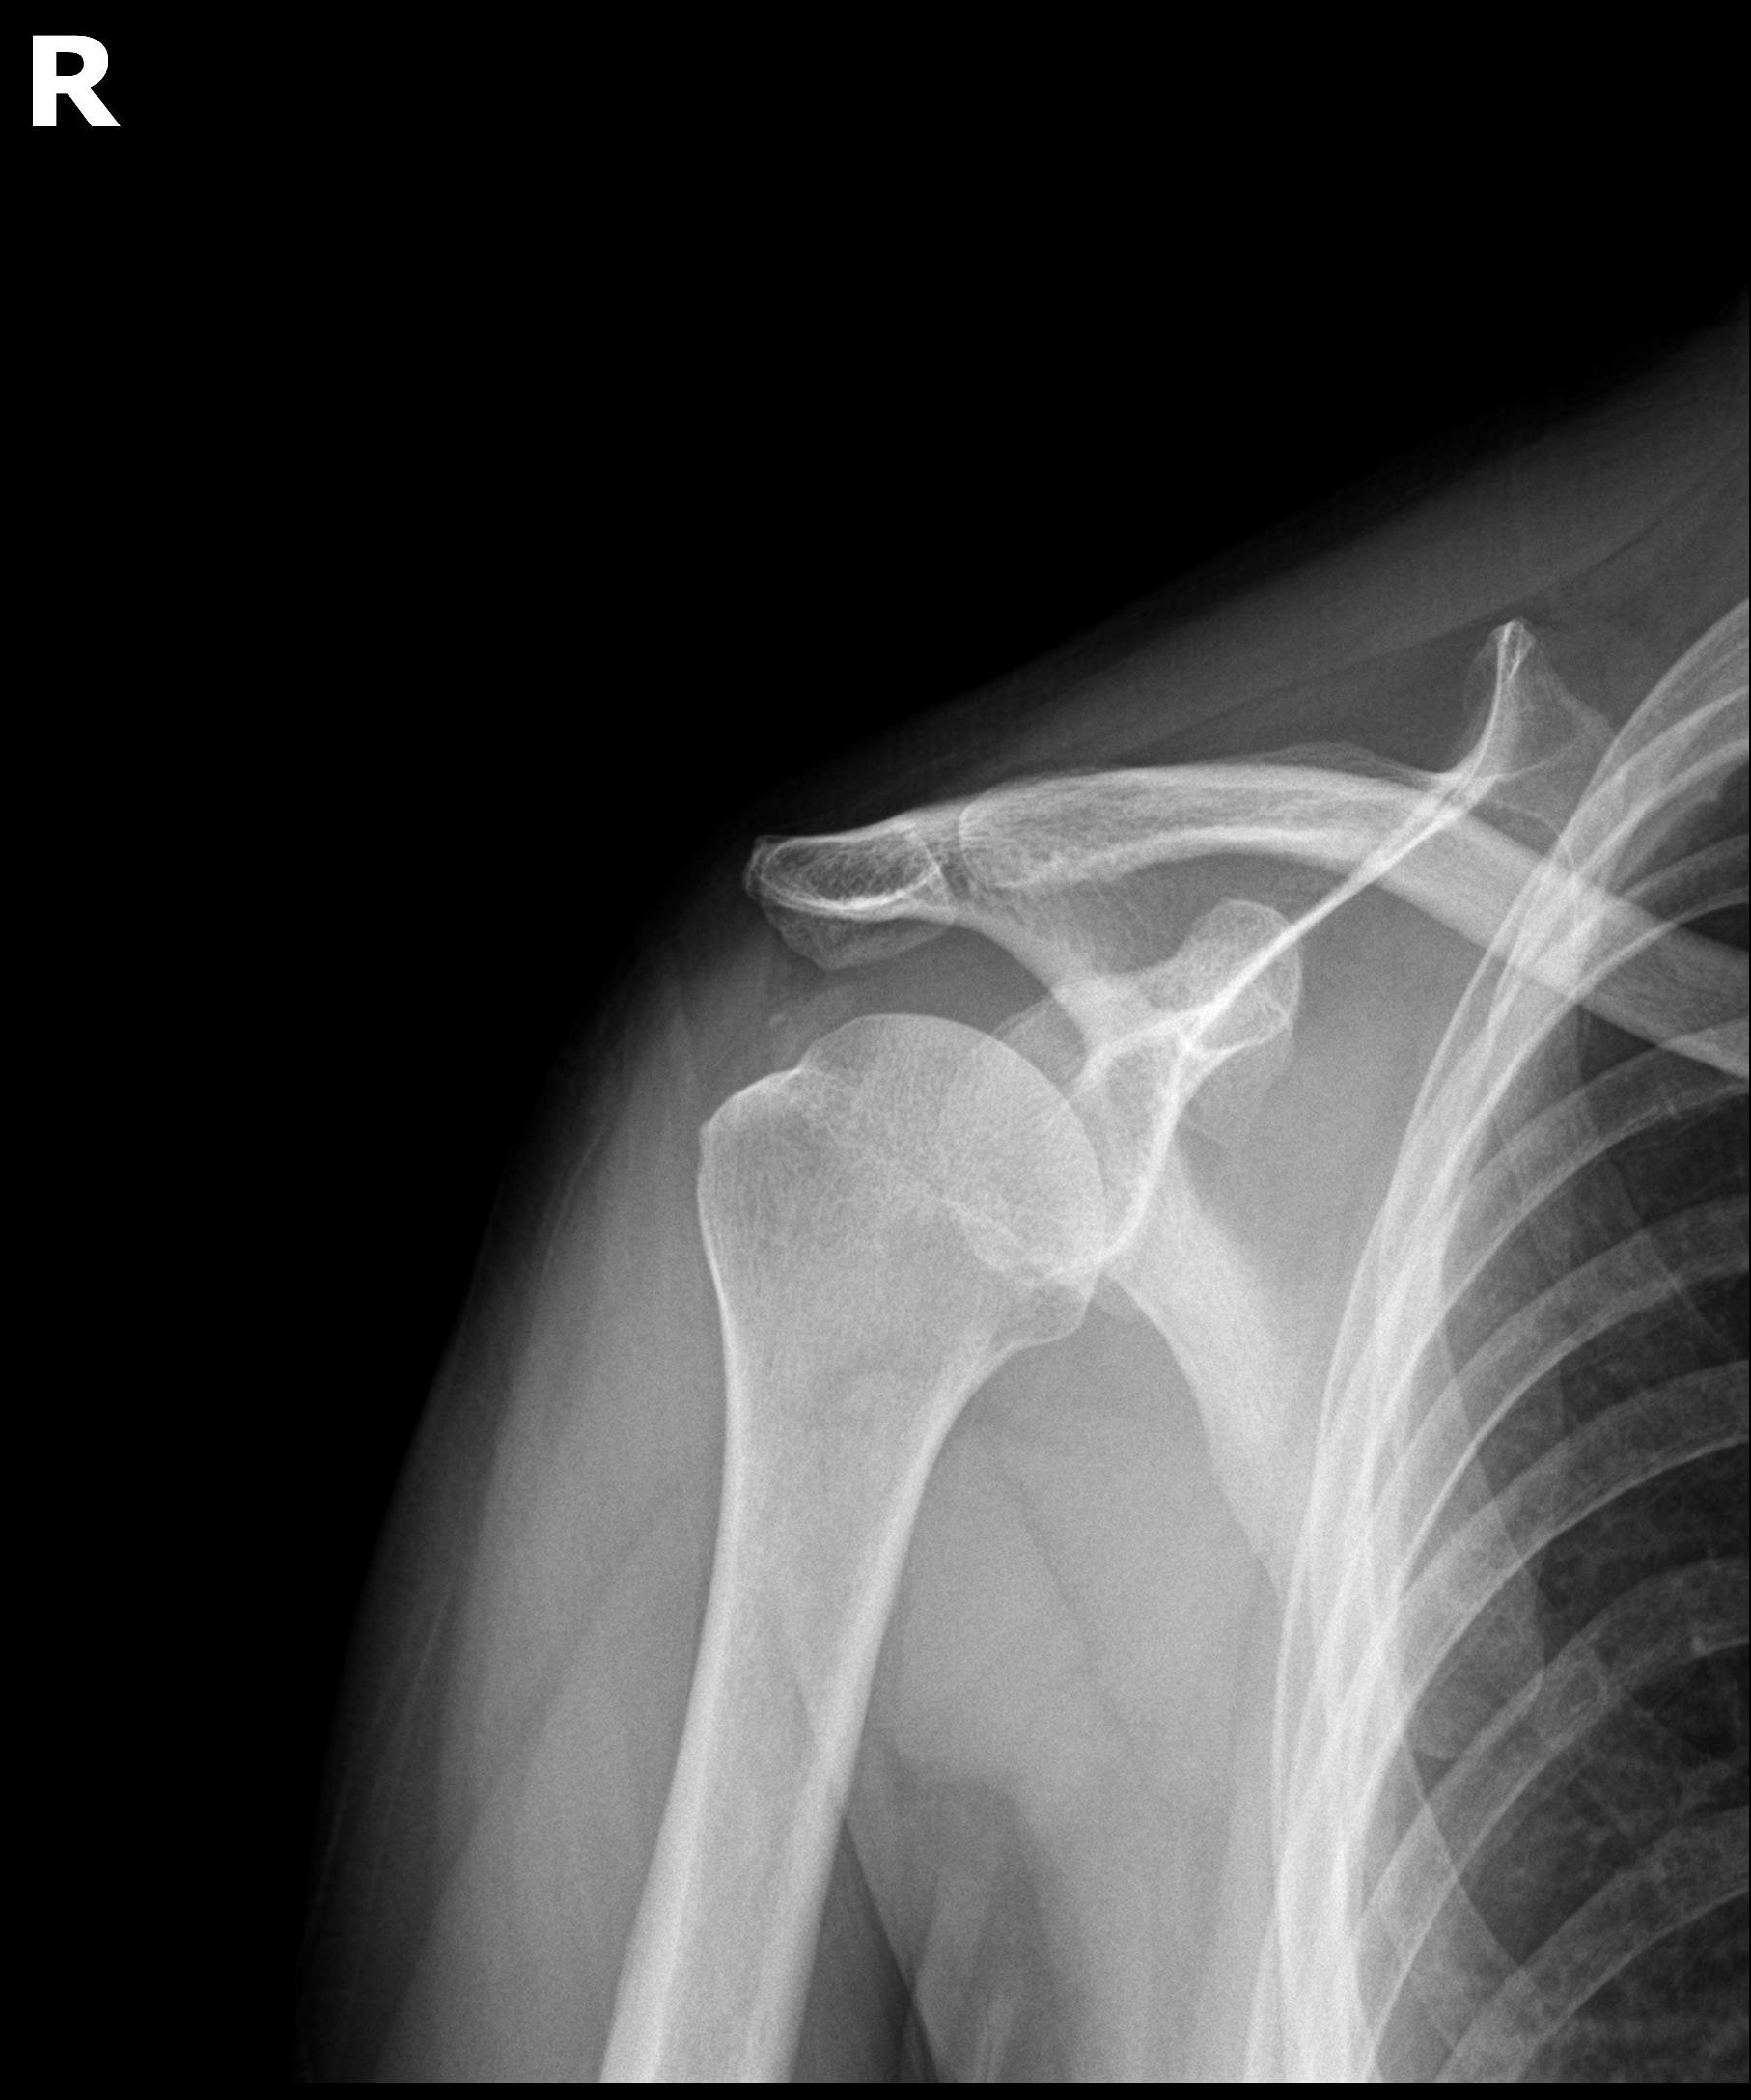

케이스 1: 형성기 단단한 석회 (1회 제거)

환자: 50대 남성, 우측 어깨 통증 8개월

시술 전:

X-ray에서 약 1.5cm 크기의 석회 확인

형성기 석회 (매우 단단)

타 병원에서 "수술 권유" 받음

시술 후:

1회 분쇄흡입술로 완전 제거

시술 직후 X-ray에서 석회 없음 확인

타 병원 시술 실패 원인 분석

환자분이 가져오신 이전 병원의 영상 자료를 검토했습니다.

문제점:

1세대 방법 사용: 주사바늘로 찌르고 씻어내는 방식

단단한 석회: 형성기~휴지기 석회였음

인대 손상: 반복 시술로 인대 주변 염증 발생

석회 잔존: 3회 시술 후에도 석회 대부분 남아있음

플래티넘에서의 치료

진단:

X-ray: 약 1.3cm 석회 (휴지기)

초음파: 석회 주변 인대 염증 소견

시술:

상완신경총 차단 마취

석회분쇄흡입술 시행

시술 시간: 35분

결과:

시술 직후 X-ray에서 석회 완전 제거 확인

기존 인대 염증은 재생주사로 추가 치료